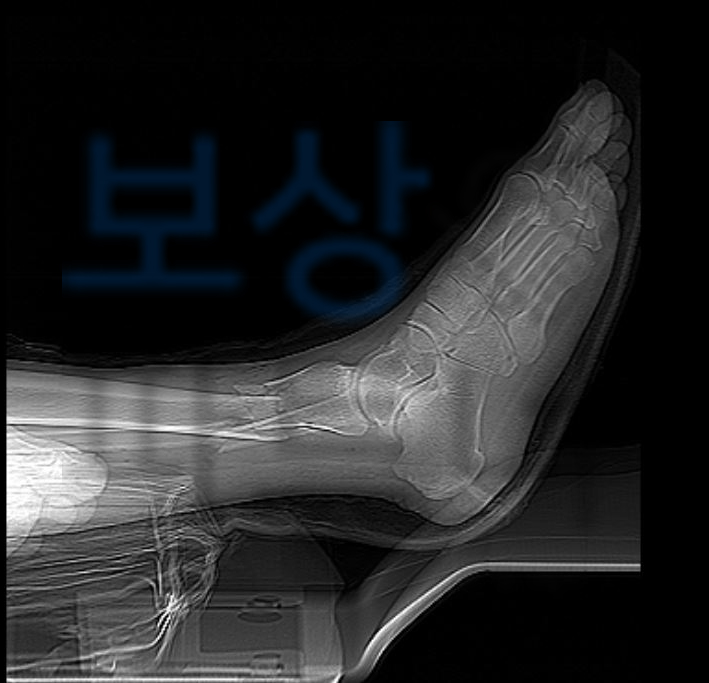

위 기록지를 보시면 엑스선 상으로

Rt talus open comm fx.

->오른쪽 거골의 개방성 분쇄골절

Lt distal tibiofibular comm fx.

->왼쪽 경비골 분쇄골절

이 확인되어 수술이 불가피 하였죠.